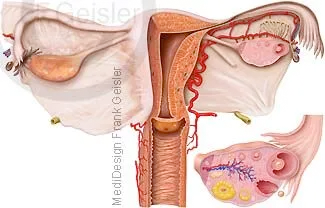

Das mandelförmige Ovar liegt intraperitoneal, ist allgemein 3 bis 5 cm lang und hat eine Dicke von 0,5 bis 1 cm. Es wird durch mehrere Haltebänder schräg am Beckeneingang fixiert. In diesem Organ erfolgt die Reifung und Bereitstellung der Eizellen, die in der Zeit zwischen dem Eintritt der Geschlechtsreife (Menarche) und dem Klimakterium durch den monatlichen Eisprung (Ovulation) ausgestoßen werden. Dabei erreicht ein Tertiärfollikel oder Bläschenfollikel (Graaf-Follikel) die Oberfläche des Ovars und platzt (Eisprung). Die Fransen (Fimbriae) des Eileiters umgreifen den Eierstock an der Stelle, wo wo der Eisprung stattfindet, um das ausgestoßene Ei aufzunehmen. Der Flimmerstrom und der Sog im Eileiter bewirken die Weiterleitung in Richtung Uterus.

Der Eisprung selbst dauert 3 bis 5 Minuten. Normalerweise erreicht die Eizelle zunächst die Ampulle des Eileiters, wo die mögliche Befruchtung stattfindet. Eine Eizelle soll nur 6 bis 24 Stunden befruchtungsfähig sein, während für Spermien im Eileiter 2 bis 4 Tage angegeben werden. In Ausnahmefällen kann der Aufnahmemechanismus in den Eileiter unterbleiben, so dass es bei einer Befruchtung zur Bauchhöhlenschwangerschaft (Extrauteringravidität) kommt. Die meisten Bauchhöhlenschwangerschaften entwickeln keinen Fötus. Die häufigste Extrauterinschwangerschaft ist die Eileiterschwangerschaft.

Der Restteil des geplatzten Follikels wird im Eierstock zum Gelbkörper (Corpus luteum) und gibt die Gelbkörperhormone (Progesteron) ab, während vor der Ovulation im Ovar die Bildung von Follikelhormonen (Estrogene) erfolgt. Diesen zweiphasigen ovariellen Zyklus von etwa 28 Tagen reguliert der Hypothalamus mit Steuerhormonen, die auf die Hypophyse wirken. Diese regt in der ersten Zyklushälfte mit ihrem follikelstimulierenden Hormon (FSH) das Ovar zur Produktion der der Follikelhormone an.

Schnittdarstellung Scheide und Gebärmutter mit Eileiter und Eierstöcke, Eireifung und Follikelsprung; Vulva erregt mit Kitzler und Uterus; Klitoris, ein aus Schwellkörpergewebe bestehendes Lustorgan der Frau